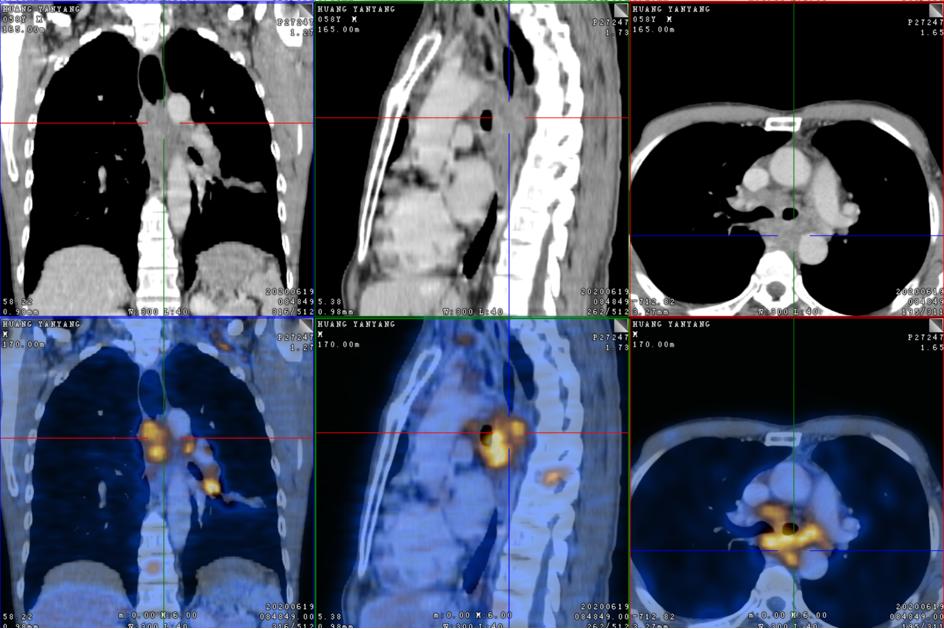

2020-6-19患者行全身PET/CT示:

1、左下肺前内基底段支气管开口处结节,糖代谢增高,考虑中央型肺癌并远端阻塞性炎症、不张;全身(双侧颈部、双侧锁骨上下窝、两侧肺门、纵隔、贲门旁、胰头后方、腹主动脉旁及双侧髂血管旁)多发淋巴结转移;双肺多发转移;肝S4及S5转移;胰头部结节转移;全身多发骨转移;综上,建议活检除外结核。

2、甲状腺双侧叶多发结节,糖代谢增高,不除外恶性肿瘤,建议追踪。左侧肾上腺稍增粗,糖代谢轻度增高,建议追踪。